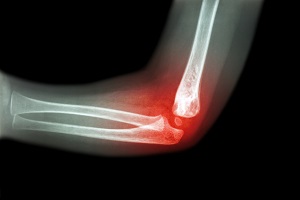

Distal Humerus Fractures of the Elbow

Injury in the distal humerus can cause impairment in the function of the elbow joint. A distal humerus fracture is a rare...